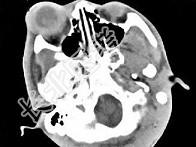

- 单项选择题女,24岁, 发热畏寒数天,右眼睛疼痛, PE:右眼睑肿胀, 结膜充血,伴右眼突出, CT如图所示,最可能的诊断是 ( )